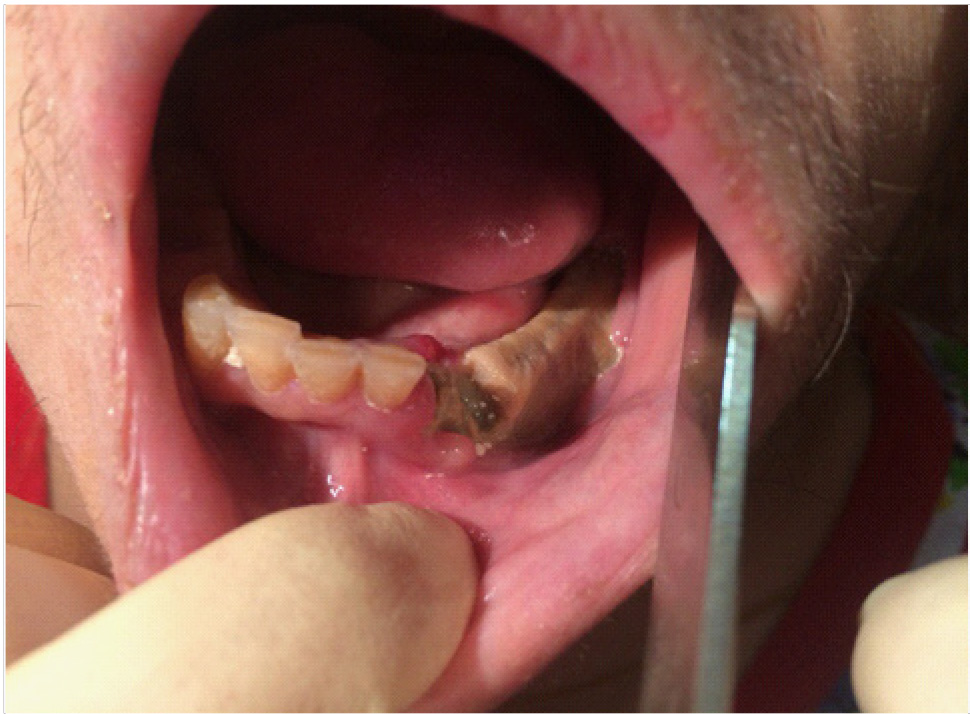

За период лечения пациентки Б. было выполнено хирургическое лечение в следующем объеме: кюретаж лунок удаленных зубов, частичная секвестрэктомия, резекция альвеолярной части нижней челюсти справа, вскрытие и дренирование гнойных очагов в стадии обострения патологического процесса. Отмечалось улучшение клинической и рентгенологической картины в полости рта (рис. 5, 6).

Рис. 5. Клинические проявления бисфосфонатного остеонекроза нижней челюсти справа у пациентки Б. в 2024 году